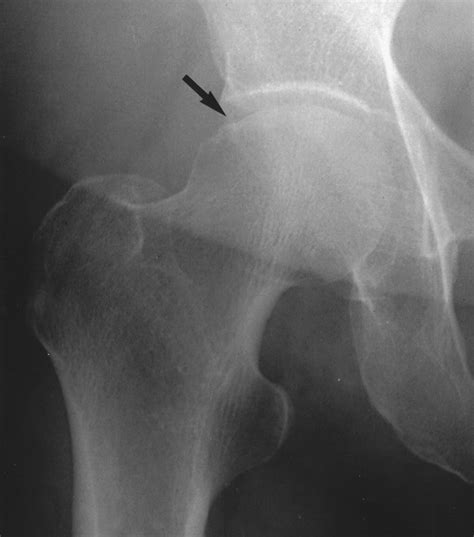

Diagnosing a hip stress fracture can be challenging because early stress fractures often do not show up on standard X-rays. A physician will typically start with a physical examination, checking for tenderness in the groin and evaluating how pain is triggered by specific movements.

• X-rays: While often negative in the first few weeks, they are still used as an initial screening tool.